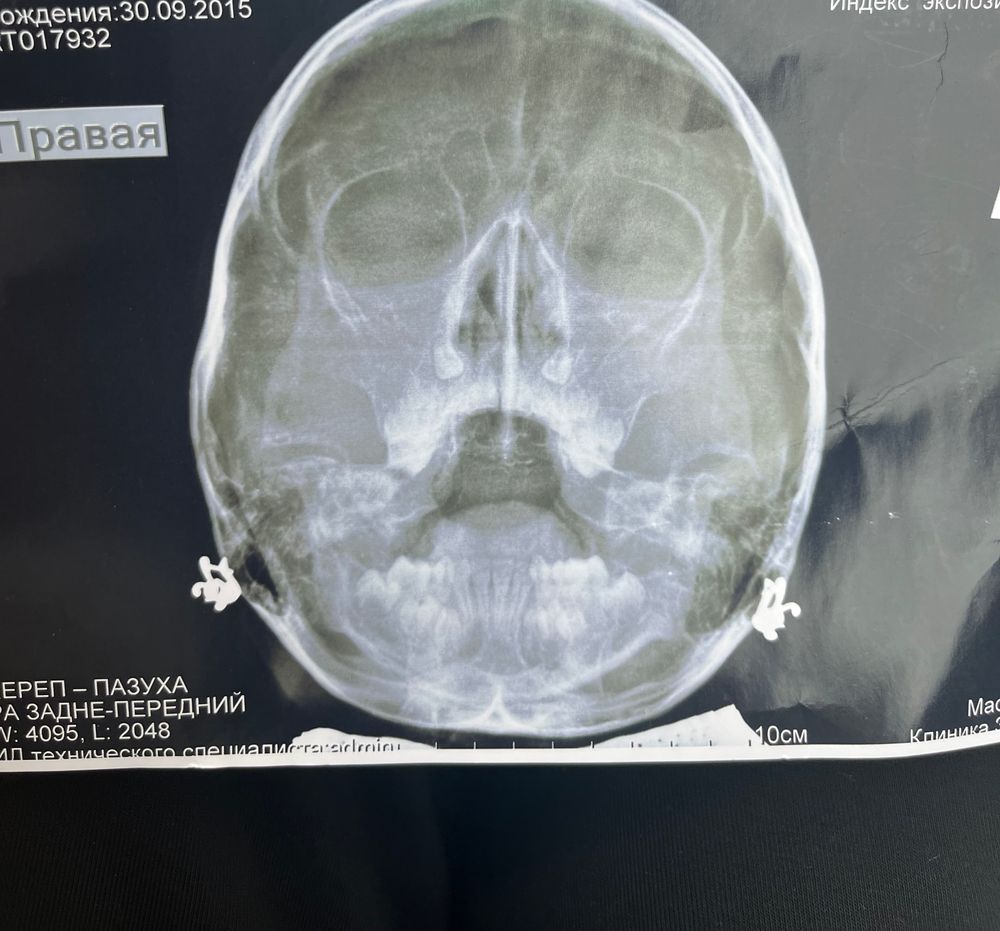

Потом выдается заключение. Как Вы сами понимаете, эти методы исследования предельно субъективны. Поэтому они обязательно должны дополняться рентгенографией носоглотки - рентген "в профиль".

Если эндоскопический осмотр проведен не был, то для постановки диагноза "гипертрофия аденоидов" необходим рентген носоглотки! ********

Собственно говоря, точно поставить степень аденоидов (а это важно для лечения) можно только после эндоскопии или рентгена. Любые другие осмотры крайне субъективны.

На рентгене аденоиды будут определяться как серая тень. Определить уровень увеличения довольно легко.